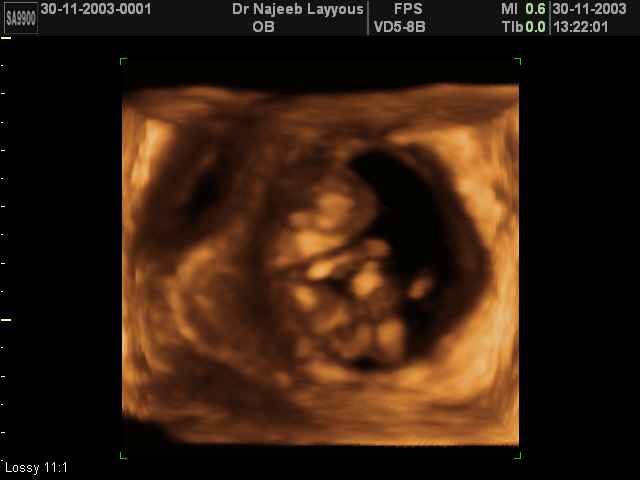

3D First Trimester Ultrasound Scan Photos